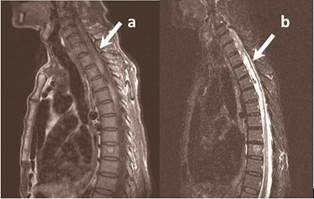

Resonancia magnética de columna (RMN) dorsal con contraste (Figura 2): se realizó dos semanas después del inicio de los síntomas pues no fue posible su realización en la fase hiperaguda de la enfermedad. Se observó una imagen es sugerente de HI subaguda tardía, que se extendía desde la zona que corresponde a la vértebra dorsal 2 (D2) hasta la que concierne a la vértebra dorsal 6 (D6). No se aprecia tumor espinal, aneurisma o malformación arteriovenosa.

El método diagnóstico más preciso es la RMN5,7 que en la fase hiperaguda (antes de 12 horas del inicio de los síntomas) se presentan como isointensos en T1 e hiperintensos en T2, además se describe la presencia de un anillo hipointenso periférico en T2. En la fase aguda (12 horas a 7 días después del inicio de los síntomas) se encuentra una señal variable y homogénea en T1 y una baja señal en T2 por presencia de eritrocitos intactos y la concentración alta de desoxihemoglobina. En la fase subaguda (7 días - 3 semanas después del inicio de los síntomas) presenta una alta señal en T1 y T2 por la formación de metahemoglobina y en la fase crónica (más de 3 semanas después del inicio de los síntomas) se evidencia una señal alta y difusa en T1 y T2.